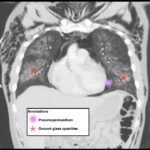

Electronic cigarette (e-cigarette) or vaping associated lung injury (EVALI) cases have increased with the popularity of e-cigarettes in the mostly young, healthy population. Some common symptoms associated with EVALI include shortness of breath and chest pain, and the most common diagnostic imaging findings are organizing pneumonia and diffuse alveolar damage seen on computed tomography (CT). Pneumomediastinum is a known sequela of EVALI.1 In the setting of pneumomediastinum in EVALI, EVALI is a diagnosis of exclusion, so other sources of pneumomediastinum need to be evaluated. EVALI has diverse presentations, and this case is a unique representation of a disease process that is becoming more commonplace with the increase in popularity of vaping. It is important to be aware of the clinical symptoms of EVALI, which can be nonspecific and can include gastrointestinal symptoms along with respiratory symptoms. It is equally important to recognize the diverse image findings of EVALI, which can include subcutaneous emphysema and pneumomediastinum. In this case, pneumomediastinum is seen in EVALI, and the patient was successfully treated with empiric antibiotic coverage, steroids, and conservative measures—making sure to limit any coughing or increases in intrathoracic pressure that can cause worsening of pneumomediastinum.

EVALI, vaping, pneumomediastinum, E-cigarette, ground-glass opacity.